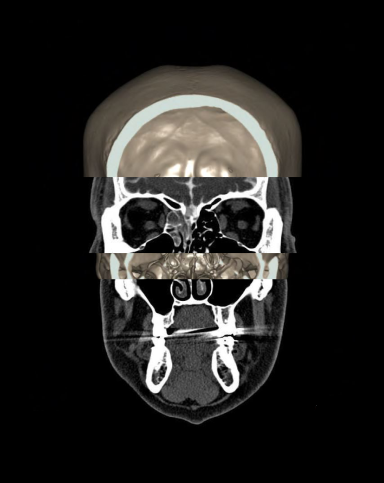

CT cisternography/ CECT cisternogram

CT Cisternogram is a contrast study used to diagnose abnormal cerebrospinal fluid (CSF) leaks-mainly into areas such as paranasal sinuses, nasal cavity (CSF rhinorrhea), middle ear cavity (CSF otorrhea), subarachnoid space and mastoid air cells.

- Axial, sagittal and coronal images in bone (WW:4500, WL: 450) and soft-tissue (WW:400, WL: 40) windows, with slice thickness lower than 2mm.